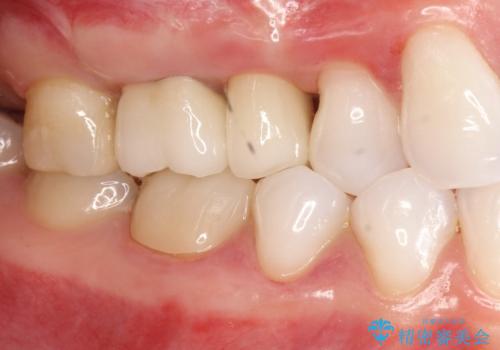

歯周外科・根管治療による長期予後を期待する奥歯の治療